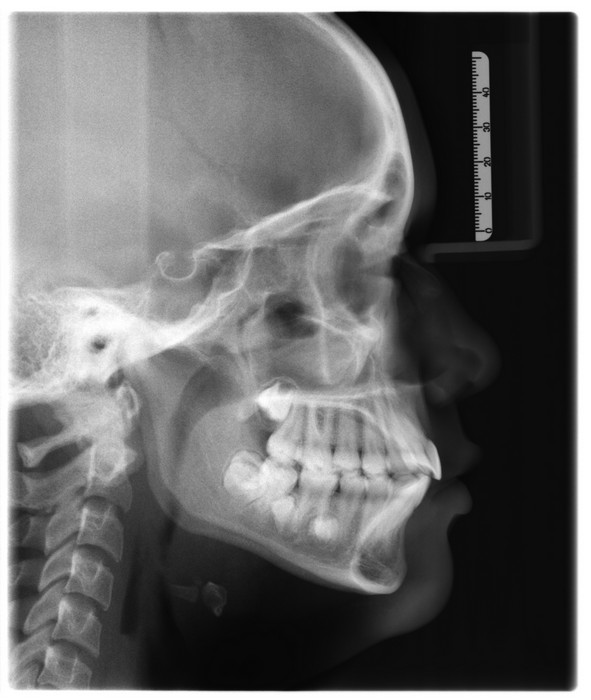

Sistemas y medios de diagnóstico de radiología digital para odontólogos, especialistas y subespecialistas en estética, ortodoncia, endodoncia, cirugía maxilar y maxilofacial, cráneo y cara, y odontología general Modelos maxilares testigos y de trabajo, fotografía clínica y diagnóstica para odontólogos generales.

En las siguientes imagenes encontrará información útil sobre la anatomía que se puede observar en una radiografía panoramica

Click sobre la imagen para ampliar